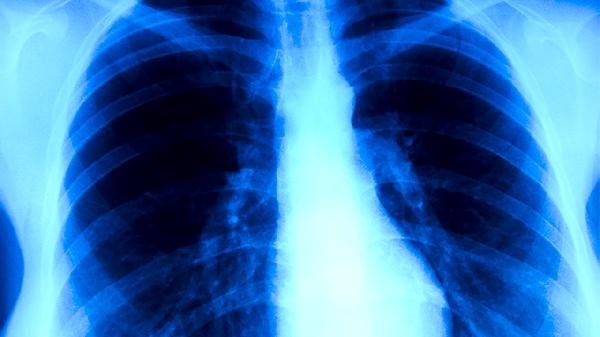

肺炎低烧可能由病毒感染、细菌感染、支原体感染、免疫反应、合并其他疾病等原因引起,肺炎低烧可通过对症支持、抗感染治疗、并发症处理、生活方式调整、定期复查等方式治疗。

肺炎低烧期间应保持室内空气流通,每日饮用温水不少于1500毫升,选择易消化的食物如粥类、蒸蛋等。避免剧烈运动但可进行舒缓活动如散步,穿着透气棉质衣物有助于散热。若低烧持续超过三天或出现呼吸急促、意识模糊等加重症状,须立即就医进行胸部X线等检查。恢复期须戒烟限酒,定期接种流感疫苗与肺炎球菌疫苗以预防复发。